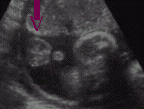

Bu gebelik haftasında yapılan bir

ultrasonda erkek bebeklerin testis ve penislerinin görülmesiyle %100

doğrulukla cinsiyet belirlenebilir. Ancak elbette gebeliğin daha ileri

haftalarına kadar ve hatta bebek doğana kadar cinsiyeti belirlenemeyen

bebekler de olabilir. Bu, bir yandan bebeğin pozisyonuyla, öte yandan

cinsiyetiyle (kız bebekler daha geç tanınır), yine ultrason cihazının ve

ultrasonu yapan kişinin özellikleriyle ilgilidir.